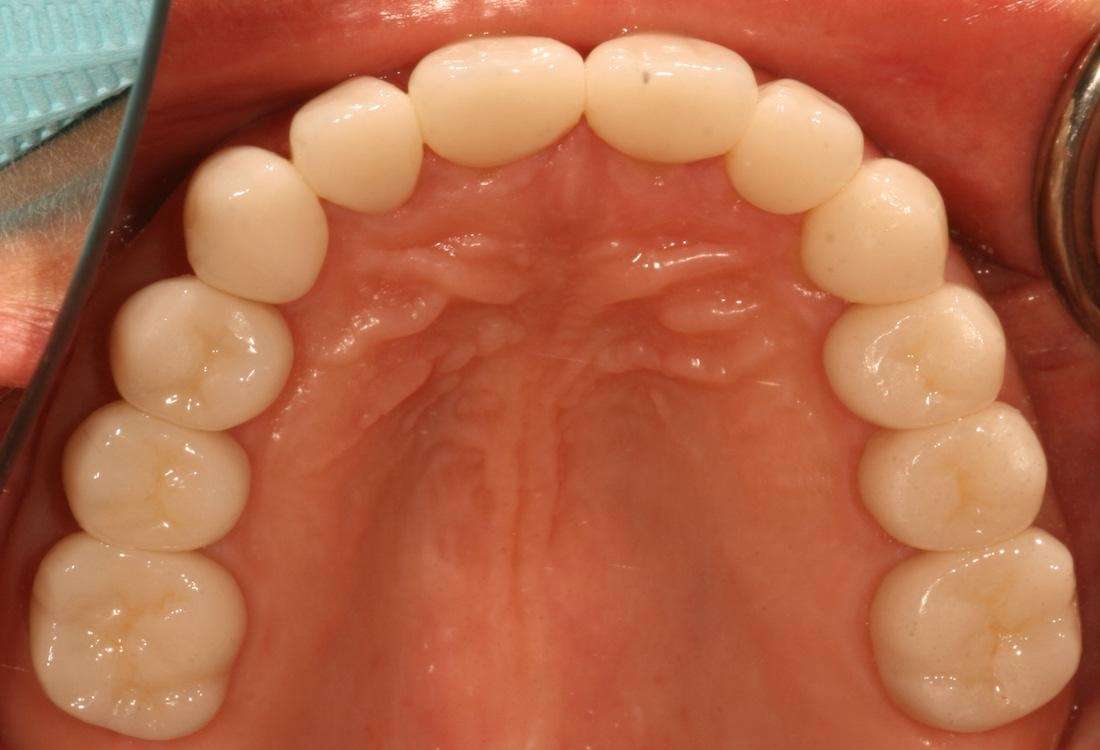

A full smile make-over has been life changing for RP. She only wishes she had done it sooner!

Before

After